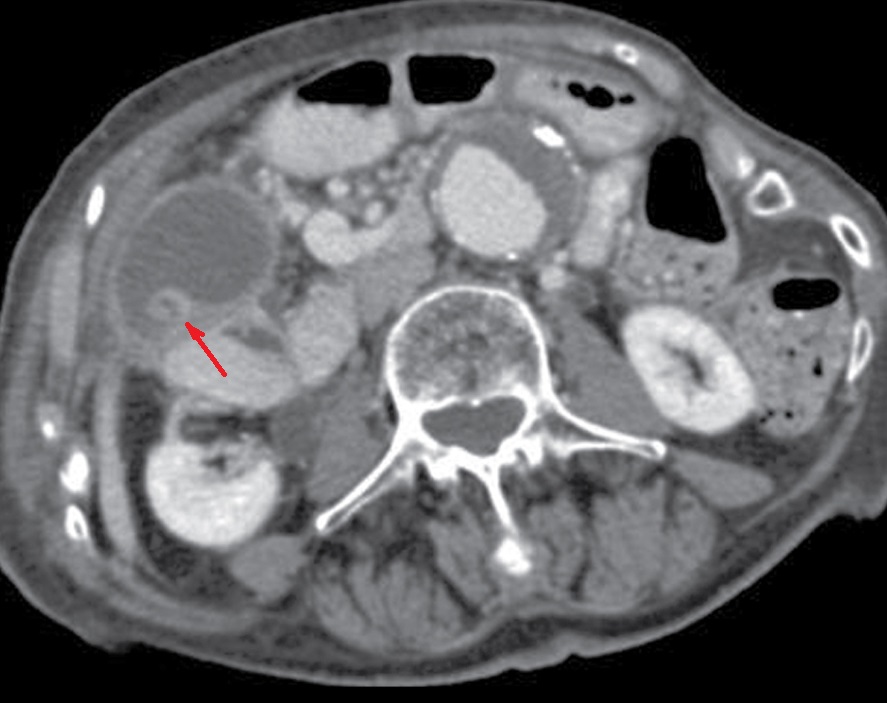

Image radiologique d'une

volvulus de la vesicule biliaire : Image de vesicule

biliaire distendue et moins de rehaussement de

contrast intravieneuse . Image TDM avec contrast

intraveineuse en coupe axiale . |

Image TDM de contrast intraveineuse en

coupe frontale : Vesicule biliaire est tres

distendue et eloigne de bord inferieure du foie . La

paroi de la vesicule biliaire est epais et en

minimum , irregulier de rehaussement de contrast (

Volvulus biliaire ) |